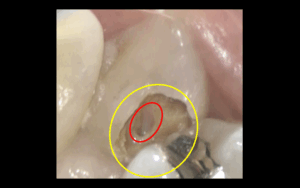

むし歯治療